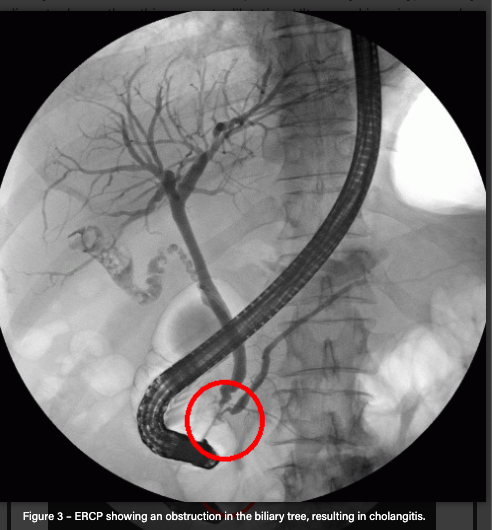

ERCP (Gold standard investigation + therapeutic)

ERCP findings

Note that many endoscopists may require MRCP prior to intervention.

Endoscopic biliary decompression to remove that cause.

ERCP with or without a sphincterotomy and stenting should clear obstruction.